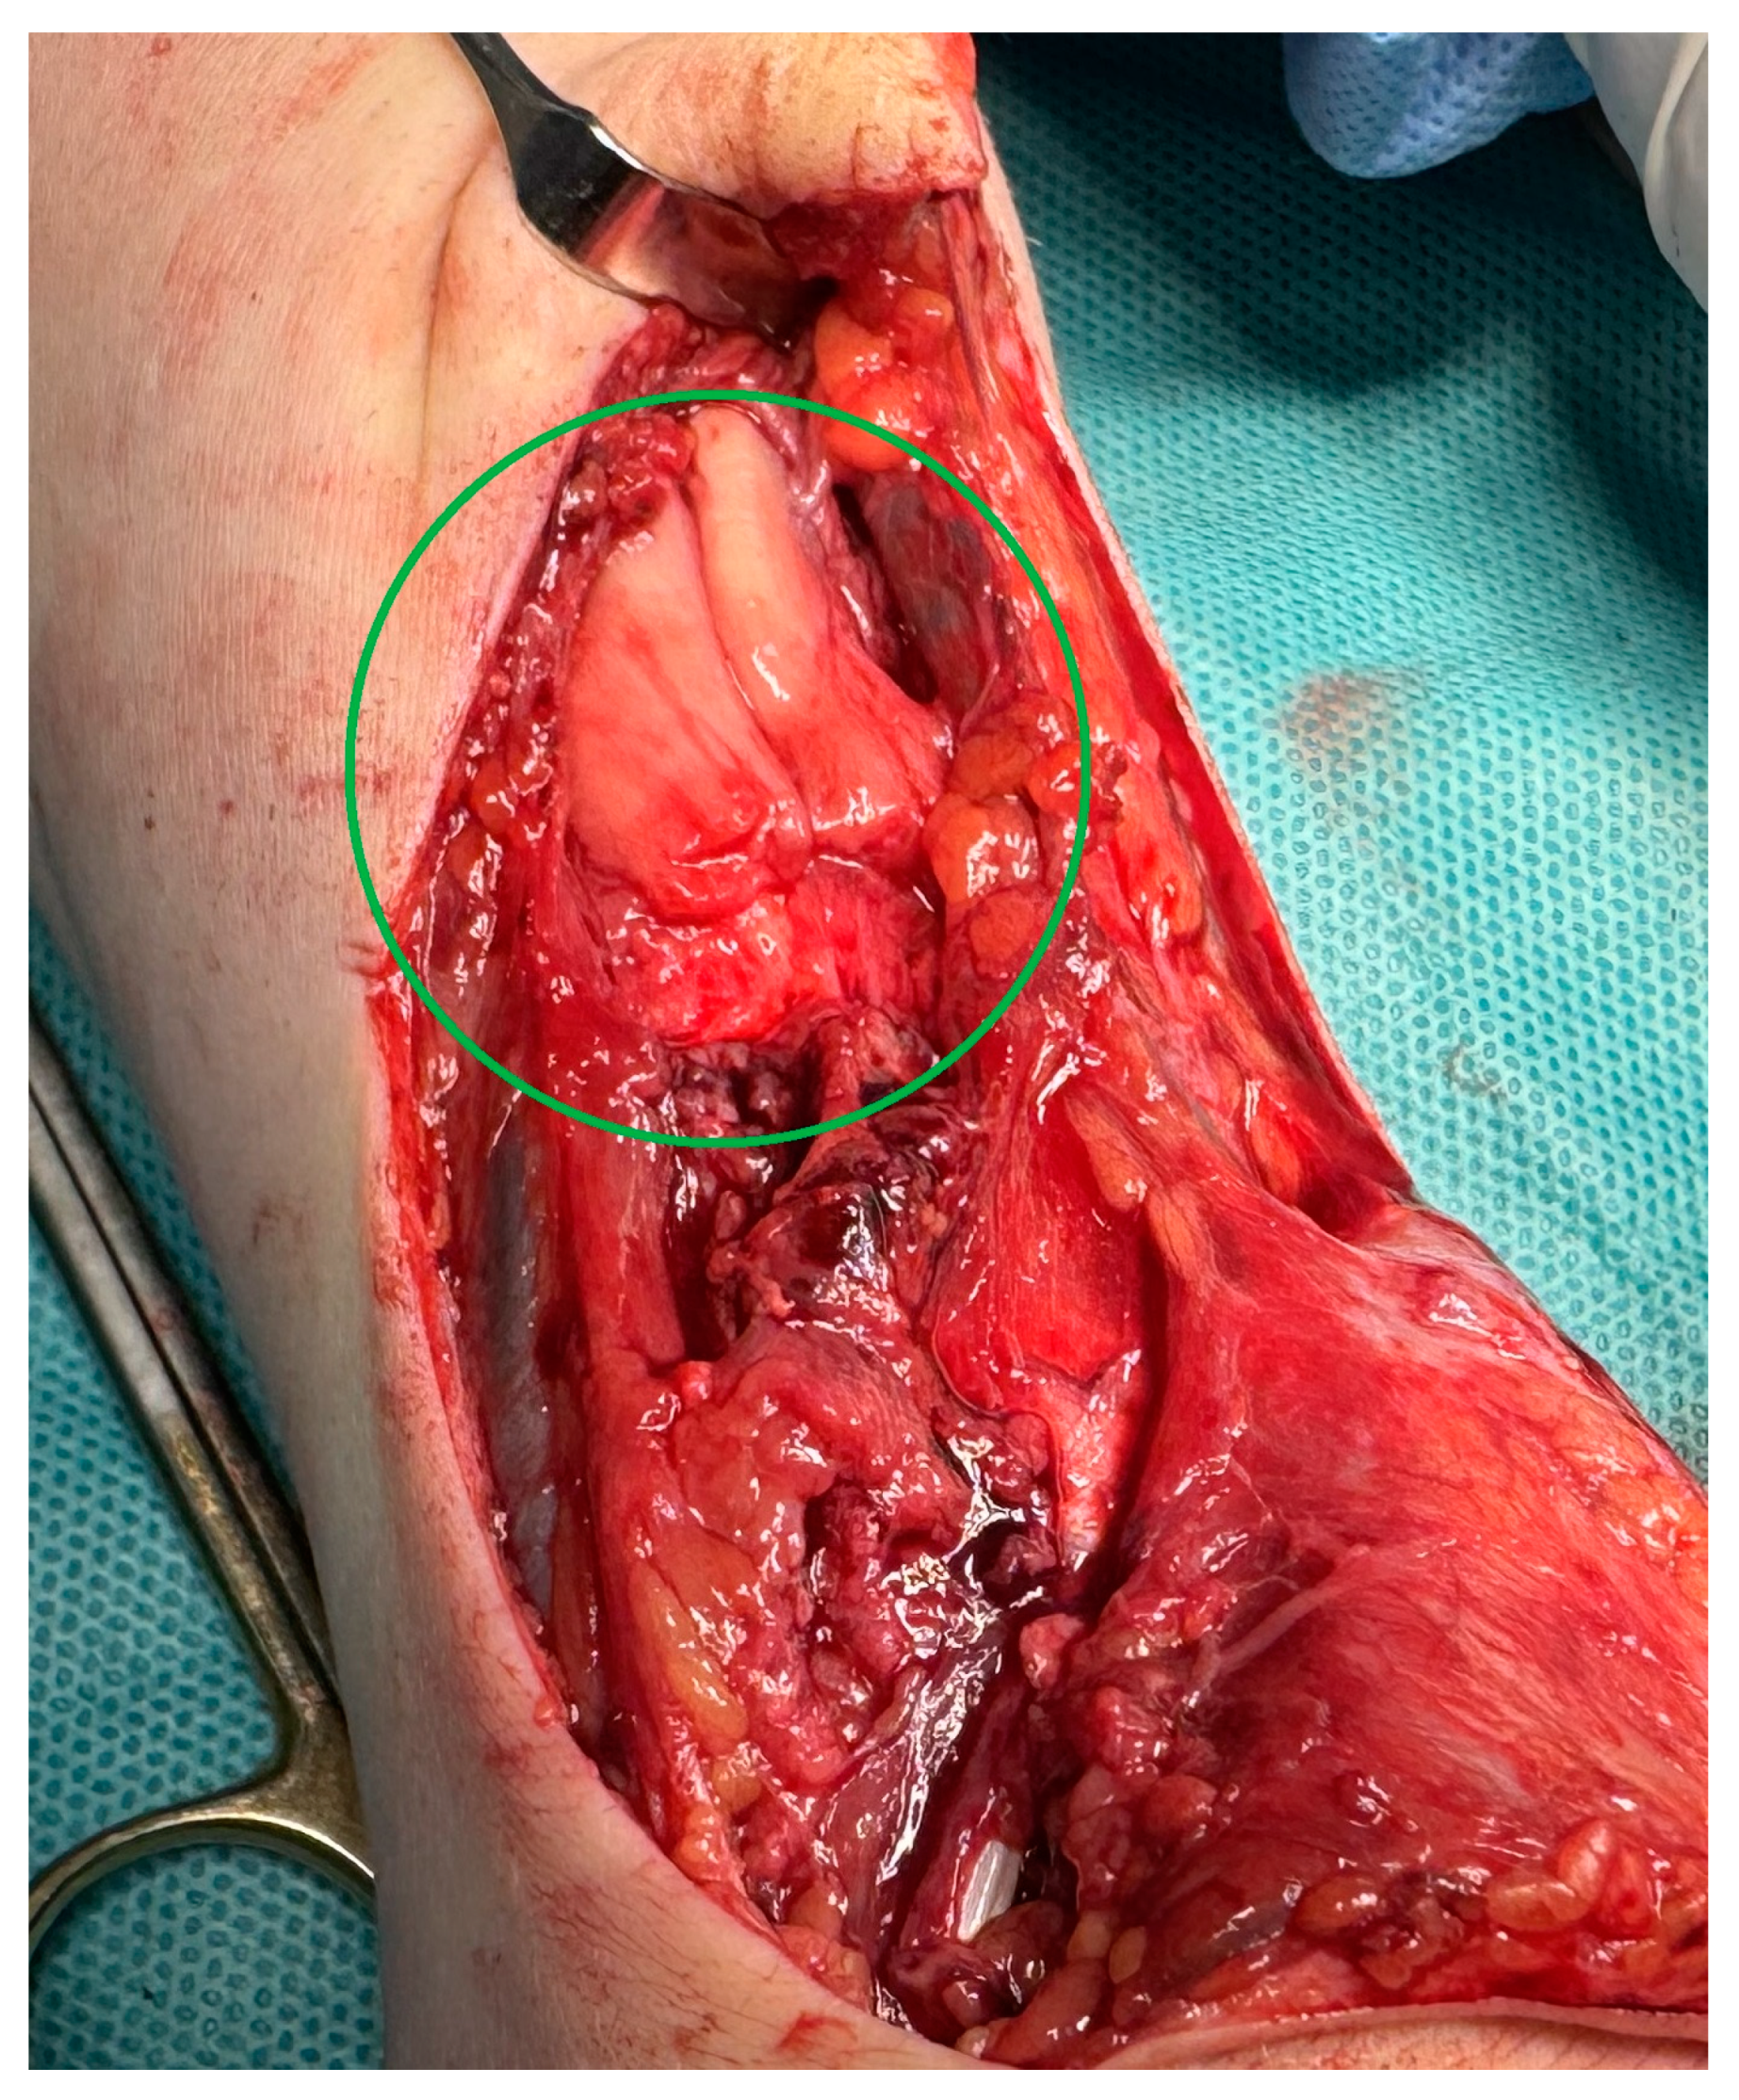

MRI scans showing the distal ends of the injured ECRL and ECRB tendons are shown in Figure 1. The extensor pollicis longus (EPL) tendon was preserved. After preparation, the patient underwent surgery. The procedure was performed under a tourniquet. The post-traumatic wound was widened proximally and distally to visualize and release scar tissue properly. After mobilization and resection of the tissue scar, the distal ends of the damaged radial extensors were visualized (Figure 2). The extent of the damage matched the MRI results. The proximal ends of the ECRL and ECRB formed a common scar and underwent retraction that did not allow mobilization (Figure 3).

Figure 2.

An intraoperative image showing the distal ends of the damaged ECRL and ECRB tendon.